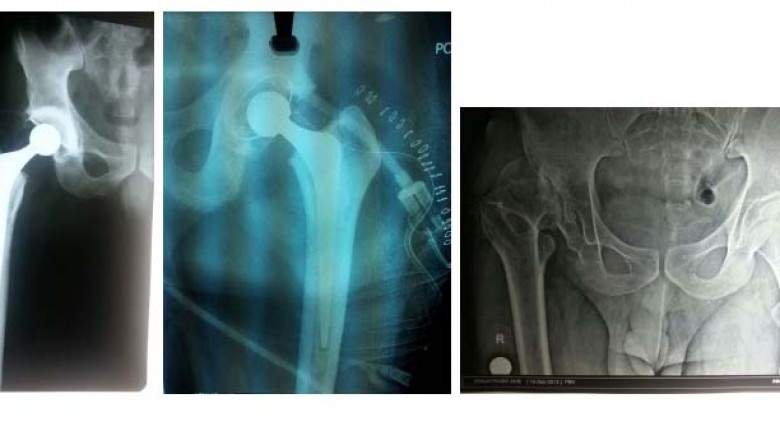

Your Best Partial Knee Replacement Surgery Clinic in Thane and the best Hip Replacement Surgeon In Thane. For info visit: https://boneandjointcare.co.in/total-hip-replacement-surgery/